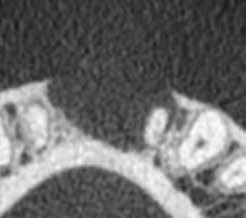

1. ábra: Kiindulási röntgenfelvétel. – 2. a–c. ábra: A horizontális irányú metszeten kiterjedt csontpusztulás jelei láthatóak (a), a vertikális irányú metszeteken mindkét középső metszőfognak megfelelően észlelhető a csontpusztulás (b–c).

3. ábra: Az eset ellátása során a „rezekciómentes” technikát alkalmaztuk. – 4. a–b ábra: Posztoperatív kontrollröntgen (a), 9 hónappal később készített kontrollfelvétel (b).

fogak elvesztését követően a rendelkezésre álló csont fiziológiás módon elkezd leépülni. Azt a folyamatot nem igazán tudjuk irányítás alatt tartani. Ugyanezzel a folyamattal szembesülünk a bakteriális fertőzések okozta parodontális megbetegedések kialakulása esetén. Vertikális irányú csontpusztulás esetén sokszor reménytelen prognózisúnak ítéljük a defektus mellett lévő fogakat. A vertikális irányú csontpusztulás mellett sokszor horizontális irányú csontveszteség is kialakul. Jelen cikknek az a célja, hogy esélyt adjon ezeknek a fogaknak a megtartására. Az itt bemutatott eljárást „rezekciómentes” technikának (zero apicectomy technique) nevezzük. A gyökércsúcs körül elhelyezkedő cisztózus elváltozások kezelését két fázisra bontja. Az elsőt magának a gyökércsatornának az ellátása jelenti. Erre gyökérkezelés és gyökértömés készítése jelenti a megoldást. A második fázis magának a cisztózus elváltozásnak és a gyökércsúcs cisztában elhelyezkedő részének az ellátásával foglalkozik. A „rezekciómentes” szemlélet a gyökércsatorna integritásának a megőrzését és az cisztaüregben lévő gyökérszakasz kezelését helyezi középpontba. Ezekben az esetekben a legnagyobb problémát az exponálódott gyökérfelszínen lévő biofilm jelenti. Ezt a terület feltárását és a ciszta eltávolítását követően egy 1%-os citromsavoldattal átitatott bondecset segítségével próbáljuk meg eltávolítani. A citromsav képes a gyökérfelszínen lévő baktériumok elpusztítására. Ilyenkor ügyelnünk kell arra, hogy ne karcoljuk meg a gyökérfelszínt és hogy a beavatkozás befejezése előtt a felvitt citromsavat bő fiziológiás sóoldatos átöblítéssel eltávolítsuk. Ezt követően 17%-os EDTA oldattal átitatott bondecsettel dörzsöljük át a területet annak érdekében, hogy az itt jelenlévő parodontális rostok regenerációját elősegítsük. Az EDTA-t 1 percig

Egy fiatal hölgy, aki modellként dolgozik és emiatt nagy jelentőséget tulajdonít a saját fogai megőrzésének, a két középső alsó metszőfoga alatt kialakult duzzanat miatt kereste fel a rendelőnket. Vizsgálatot követően megállapítottuk, hogy a fogak mellett 20 mm szélességű tasak van jelen, amely az egyik alsó középső metszőfog disztális oldalától a másik alsó középső metszőfog disztális felszínéig terjed. Ebből az következik, hogy ezen a területen a teljes bukkális kortikális csontlemez leépült. Mindkét fog III. fokú mobilitással rendelkezett, amely tovább rontotta a kérdéses fogak várható prognózisát. Szenzibilitásvizsgálatot is végeztünk. A két alsó középső metszőfog esetében a páciens nem jelzett hidegingert, de a többi fog esetében fiziológiás választ adott. Periapikális röntgenfelvétel készült, amelyen nem mutatkozott meg a vélelmezett elváltozás (1. ábra). Ennek megfelelően CBCT-felvételt készítettünk, hogy jobban meg tudjuk vizsgálni a kérdéses területet. Ezen a felvételen már láthatóvá vált a vertikális és horizontális irányú csontpusztulás tényleges mértéke. A horizontális síkban készített metszeten a két alsó középső metszőfog körül megfigyelhető volt a bukkális kortikális csontlemez és a szivacsos csontállomány hiánya. A defektus szélessége 14,11 mm, a mélysége pedig 6,28 mm volt (2. a. ábra). A vertikális irányú metszeten láthatóvá vált, hogy a középső metszőfogak gyökerének bukkális oldalát nem fedi csont, és ez a defektus már a gyökércsúcsok alatti területre is kiterjedt (2. b–c. ábra)